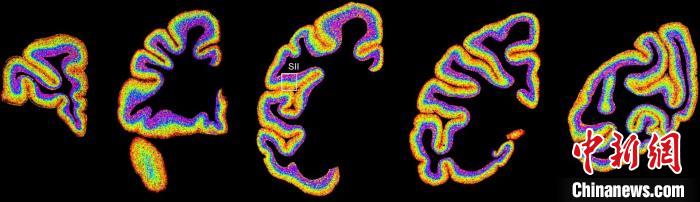

圖為不同類型細(xì)胞在獼猴大腦上的分布切片?!≈袊茖W(xué)院腦科學(xué)與智能技術(shù)卓越創(chuàng)新中心 供圖

李澄宇說,科研人員做的事情好似“查戶口”,也就是搞明白猴腦里有哪些細(xì)胞、這些細(xì)胞在哪些位置。搞明白這些就形成了一個(gè)大的數(shù)據(jù)集,科研團(tuán)隊(duì)挖掘這個(gè)數(shù)據(jù)集,發(fā)現(xiàn)了很多有意思的現(xiàn)象:比如,興奮性神經(jīng)元、抑制性神經(jīng)元以及非神經(jīng)元在大腦皮層中的分布呈現(xiàn)明顯的特異性,也就是不同細(xì)胞“住”哪,有一定規(guī)律。